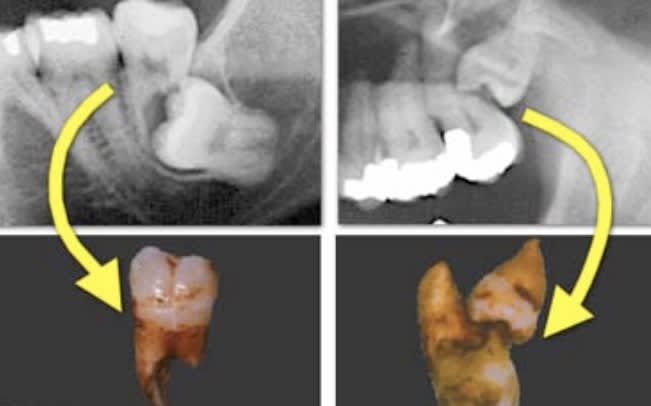

Un petit up pour confirmer que sur mes 500 derniers patients adressés ortho en vue DDS, aucun n'a eu les prémolaires d'extraites. Donc tous les orthodontistes n'adressent pas leurs patients pour avulsions préventives des DDS, la plupart posent l'indication...

En pièce jointe un patient qui n'a pas voulu écouter les consignes en 2014 et qui vient finalement de se faire opérer cette semaine.